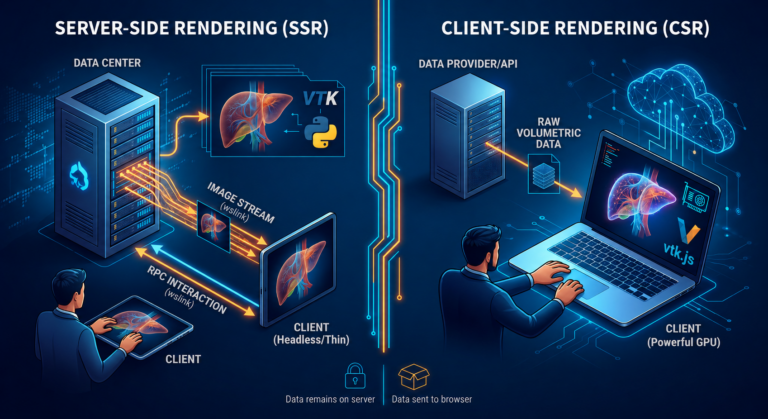

Al giorno d’oggi, un accesso rapido e semplice alle informazioni del paziente è più importante che mai. DICOM Vision si integra perfettamente con sistemi di telemedicina e cartelle cliniche online, consentendo ai professionisti sanitari di accedere agli esami diagnostici direttamente dal proprio browser internet. Questa funzionalità non solo migliora l’efficienza, ma anche la qualità delle cure fornite, rendendo il processo di diagnosi più fluido e meno soggetto a errori.